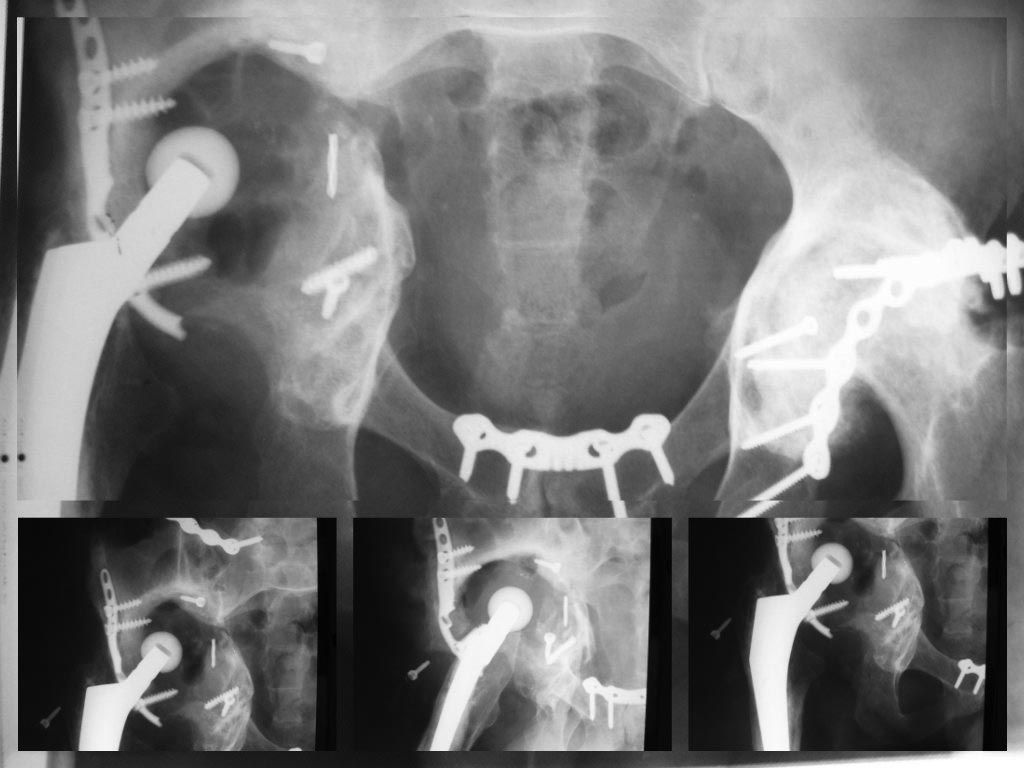

Хочу добавить картинки  выполненной операции

первая - до  операции